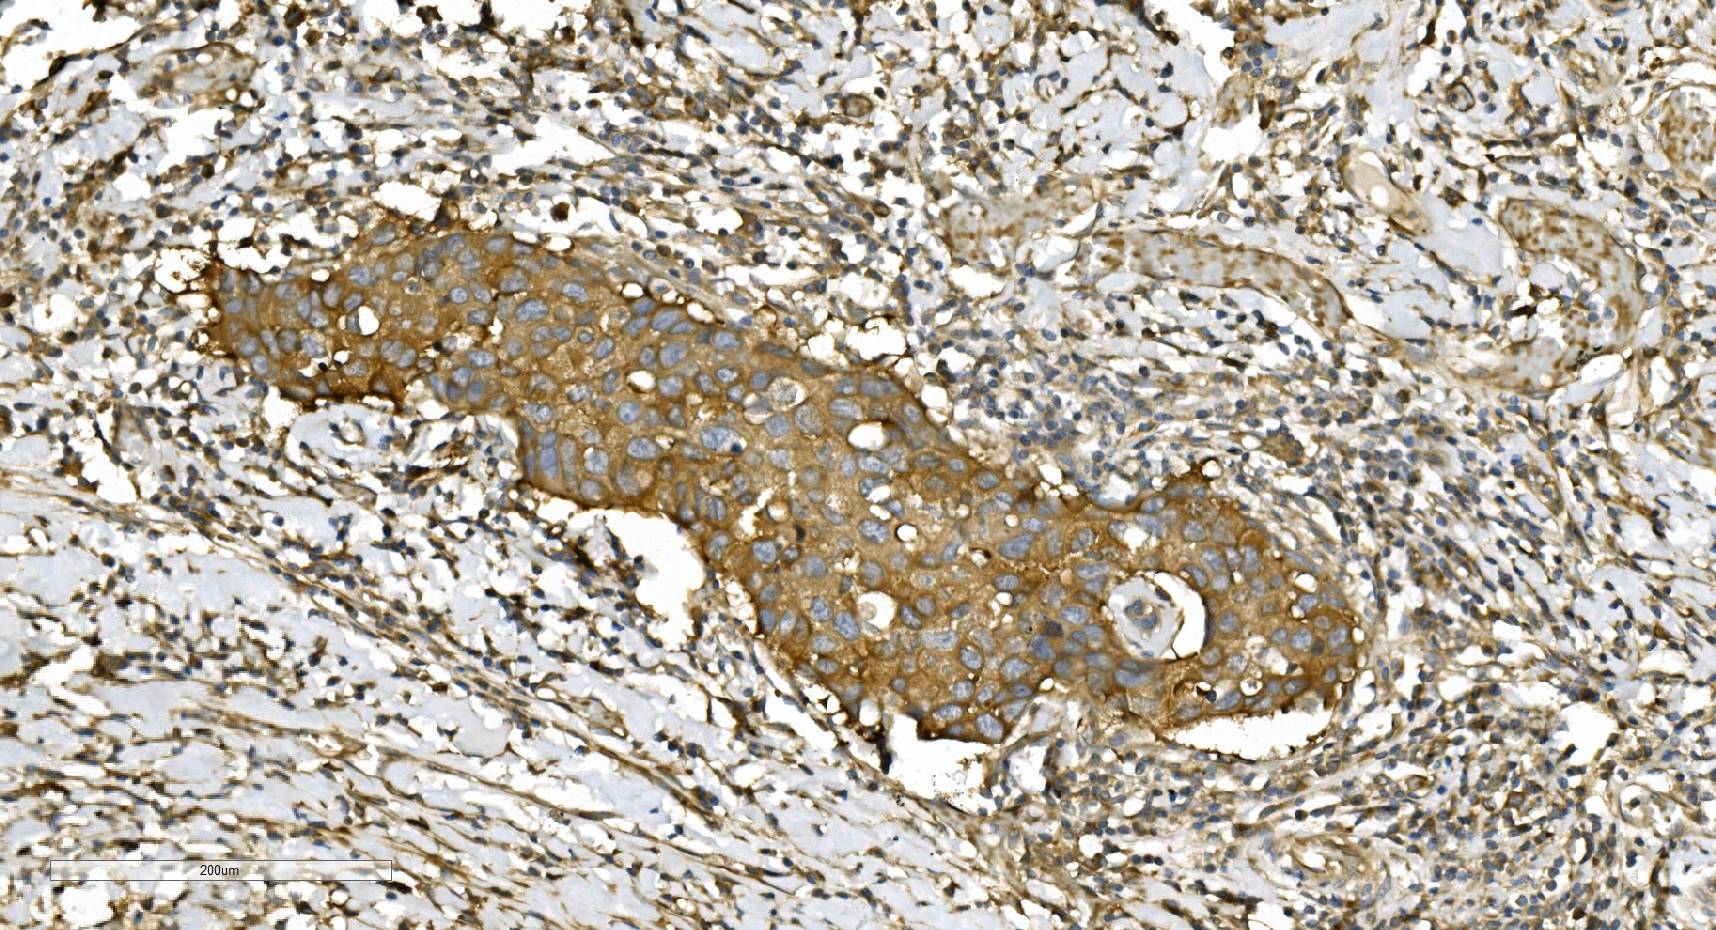

IHC analysis of Alpha Tubulin/TUBA1A using anti-Alpha Tubulin/TUBA1A antibody (M03989-3).

Alpha Tubulin/TUBA1A was detected in a paraffin-embedded section of human lung cancer tissue. Biotinylated goat anti-mouse IgG was used as secondary antibody. The tissue section was incubated with mouse anti-Alpha Tubulin/TUBA1A Antibody (M03989-3) at a dilution of 1:200 and developed using Strepavidin-Biotin-Complex (SABC) (Catalog # SA1021) with DAB (Catalog # AR1027) as the chromogen.